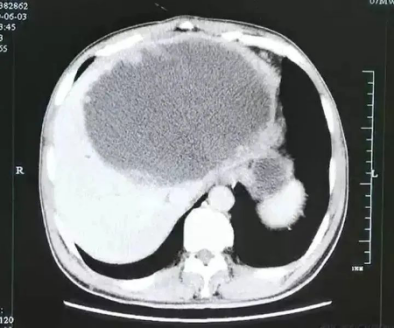

医生仔细测量了一下

大脓球达到19cm×18cm×12cm 大小

如图所示

↓↓↓

入院后腹部CT检查发现

谢先生的肝脓肿壁上

长了很多肿瘤样的结构

而且壁很厚

看来这个肝脓肿,不简单